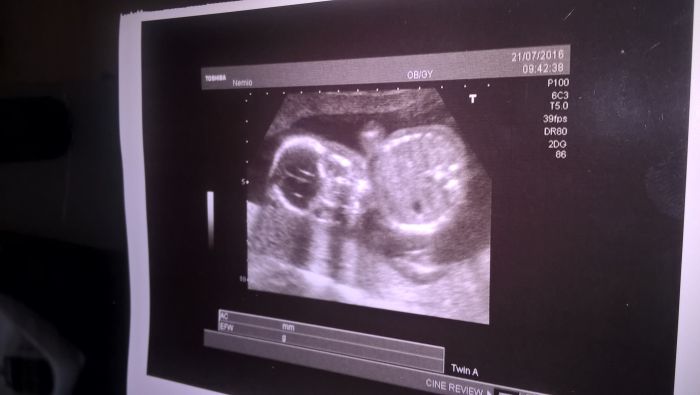

[923893] ted jsem byla na ultrazvuku u svého doktora.

Lenulacek: Jé, to je krásnej mimozemšťan! Já jsem si minulý týden nějak zapomněla říct o fotku :-) Ale vypadal podobně :-) A ještě doktor neviděl, co to bude?